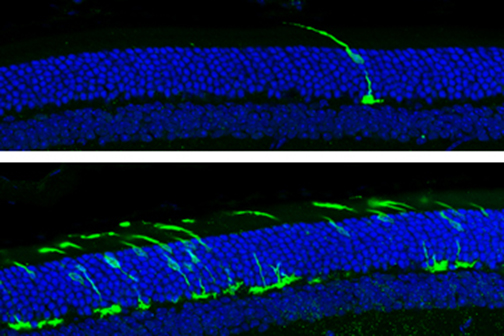

LSU Health New Orleans Study Identifies a Potential New Approach to PTSD Treatment

An LSU Health New Orleans research study led by Siqiong June Liu, PhD, Professor of Cell Biology and Anatomy, has found that cerebellar inhibitory interneurons are essential for fear memory, a type of emotional memory formation. Inhibitory interneurons within the cerebellar circuitry act as gatekeepers and control the output of the cerebellar cortex. The formation of fear memory requires the activity of these interneurons. The findings, which may lead to a novel treatment approach for post-traumatic stress disorder, are published in Cell Reports. More